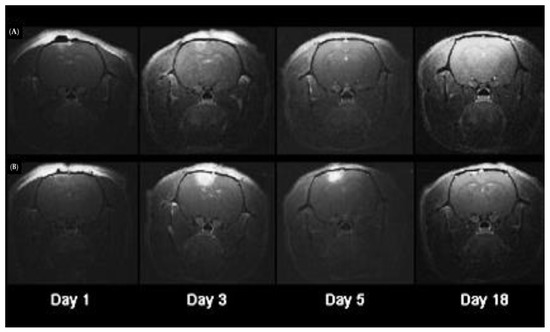

Drug Release from Loaded Ma

- Shin, D.; Christie, C.; Ju, D.; Nair, R.K.; Molina, S.; Berg, K.; Krasieva, T.B.; Madsen, S.J.; Hirschberg, H. Photochemical internalization enhanced macrophage delivered chemotherapy. Photodiagnosis Photodyn. Ther. 2018, 21, 156–162. [Google Scholar] [CrossRef] [PubMed]